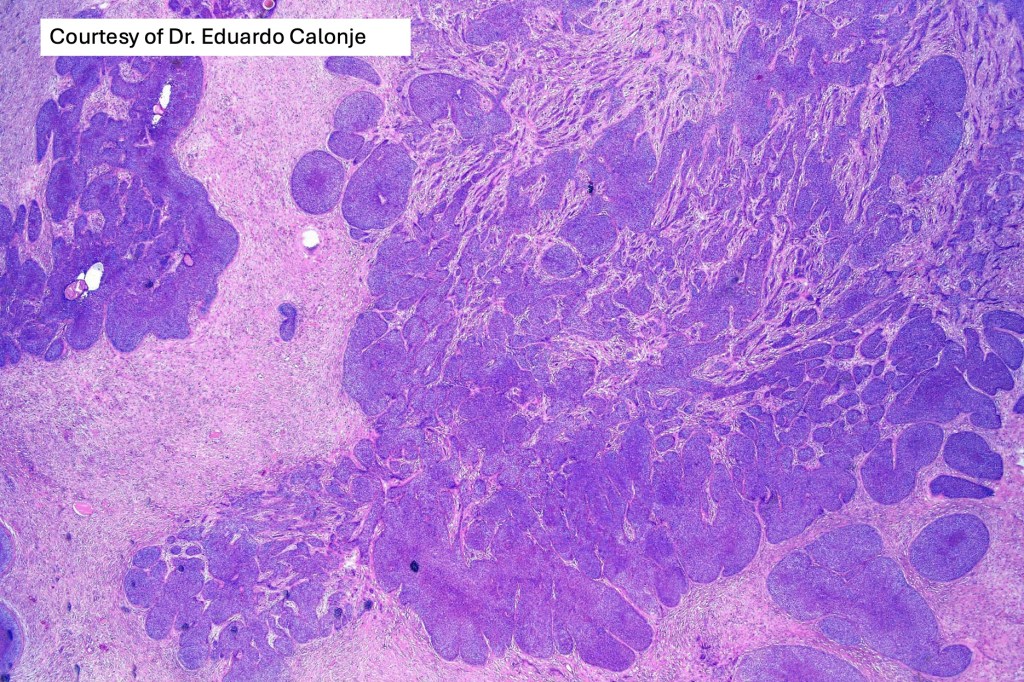

•Sharply circumscribed, unencapsulated nodule in deep dermis +/- subcutaneous fat or deeper (trichoepithelioma is much more superficial)

•Variably sized but generally large, basophilic tumor nodules composed of small uniform basaloid cells with minimal cytoplasm

•Peripheral palisading but no retraction artifact or stromal mucin deposition

•A rich fibromyxoid mesenchymal stroma with variable papillary mesenchymal bodies (sometimes these are absent)